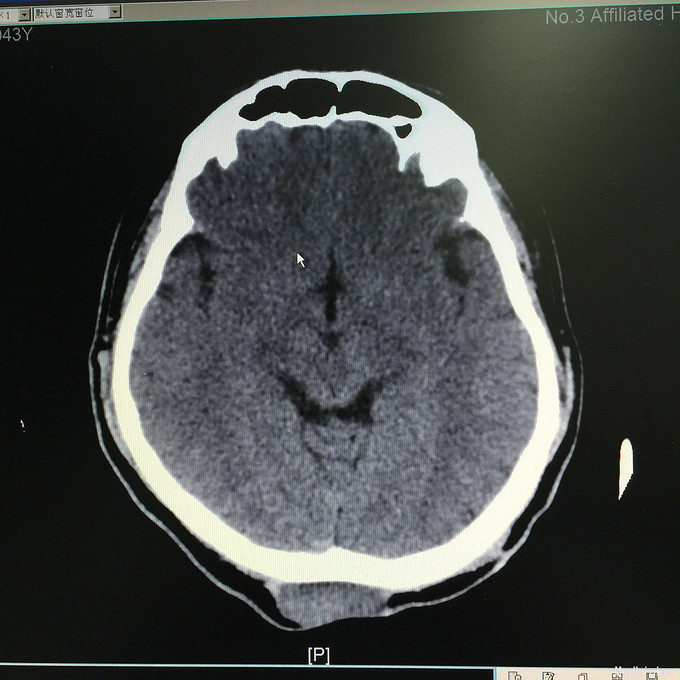

查体:头枕部可见单个肿物,半圆形,约鸡蛋大小,质地中等,边界清,无糜烂、渗出、压痛。头枕部可见单个半环状手术疤痕,长约15cm,无糜烂、渗出、脓性分泌物,无恶臭。余查体无特殊。 辅助检查:抽血检查未见明显异常。头颅CT增强示:“低度恶性纤维黏液样肉瘤”切除术后,枕部皮下软组织影,结合病史,考虑肿瘤复发,建议MR检查。彩超:双侧颈部见多个小淋巴结,双侧腋窝未见明显异常肿大淋巴结。双侧腹股沟见多个小淋巴结。